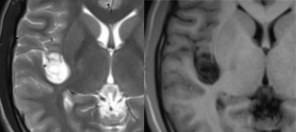

case 4:23Y/F,右岛叶占位:胚胎发育不良性神经上皮肿瘤,WHOⅠ级。

MRI:右侧岛叶多房囊状异常信号,边缘清楚,「瘤内分隔」,T1WI 低信号,T2WI 高信号,Flair「环形征」;PET-CT:低密度灶,低代谢。